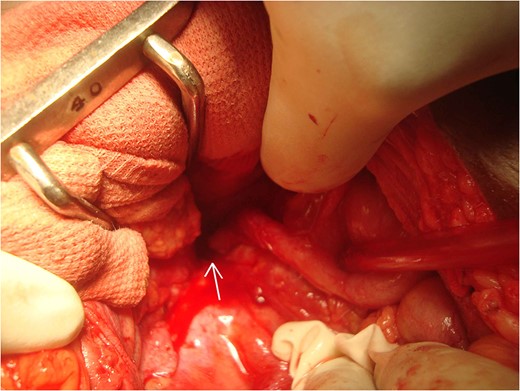

On laparotomy an inflamed, thick, retrocaecal perforated appendix tip densely adhered to a small retroperitoneal cavity over the right psoas muscle was seen (Fig. 3). This was communicated with thick-walled fistulous tract traversing along postero-lateral abdominal wall and opening externally in right lumbar region near anterior end of one of the surgical scar. Appendectomy along with excision of cutaneous fistulous tract was done. Post-operative course was uneventful. The patient has shown no recurrence after 1 year of surgery.

Intraoperative image showing retrocaecal appendix with tip adhered to psoas muscle.